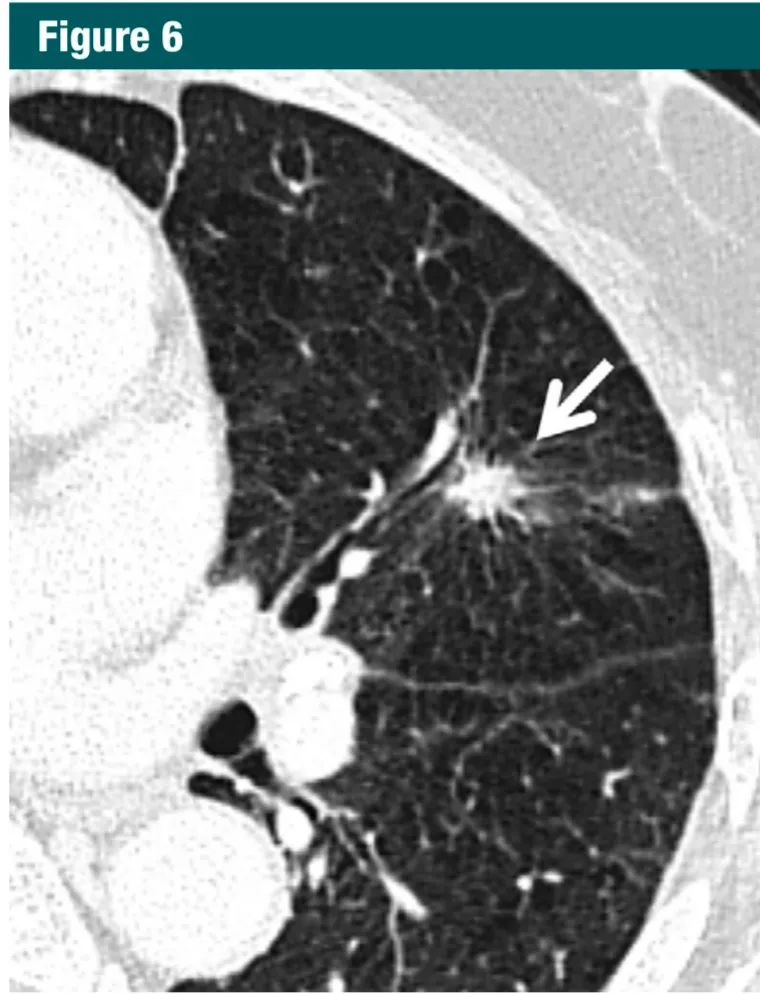

对于>8mm 的孤立实性非钙化结节,考虑3 个月后随访,作出诊断需要结合 PET 和 CT,组织取样,或选择上述方法的组合。需适当的依据大小、形态、伴随疾病和别的因素作出选择哪种方法(1A级:强烈推荐,高质量证据)。虽然 8mm 的实性结节的平均患癌风险仅仅为约3%,具体依赖于形态和位置,但在某些特定患者中,风险可以明显高于该百分比。当结节增大、它们的形态变得更加清楚,对其处理策略依据结节的表现较大小更为重要(图5-7)。因此,本指南包括了有创和无创的处理选择。

图6:横断面扫描1mmCT层面,左上肺显示一可疑的毛刺状实性结节(箭头);术后病理为浸润性腺癌7Gc帝国网站管理系统